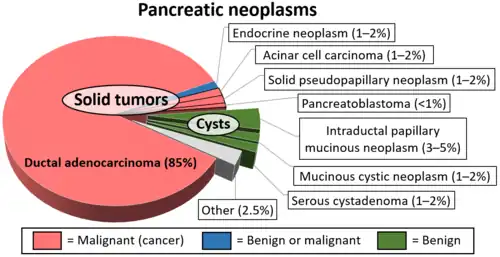

Cancer

Pancreatic cancers, particularly the most common type, pancreatic adenocarcinoma, remain very difficult to treat, and are mostly diagnosed only at a stage that is too late for surgery, which is the only curative treatment. Pancreatic cancer is rare in people younger than 40 and the median age of diagnosis is 71.[29] Risk factors include chronic pancreatitis, older age, smoking, obesity, diabetes, and certain rare genetic conditions including multiple endocrine neoplasia type 1, hereditary nonpolyposis colon cancer and dysplastic nevus syndrome among others.[27][30] About 25% of cases are attributable to tobacco smoking,[31] while 5–10% of cases are linked to inherited genes.[29]

Pancreatic adenocarcinoma is the most common form of pancreatic cancer, and is cancer arising from the exocrine digestive part of the pancreas. Most occur in the head of the pancreas.[27] Symptoms tend to arise late in the course of the cancer, when it causes abdominal pain, weight loss, or yellowing of the skin (jaundice). Jaundice occurs when the outflow of bile is blocked by the cancer. Other less common symptoms include nausea, vomiting, pancreatitis, diabetes or recurrent venous thrombosis.[27] Pancreatic cancer is usually diagnosed by medical imaging in the form of an ultrasound or CT scan with contrast enhancement. An endoscopic ultrasound may be used if a tumour is being considered for surgical removal, and biopsy guided by ERCP or ultrasound can be used to confirm an uncertain diagnosis.[27]

Because of the late development of symptoms, most cancer presents at an advanced stage.[27] Only 10 to 15% of tumours are suitable for surgical resection.[27] As of 2018, when chemotherapy is given the FOLFIRINOX regimen containing fluorouracil, irinotecan, oxaliplatin and leucovorin has been shown to extend survival beyond traditional gemcitabine regimens.[27] For the most part, treatment is palliative, focus on the management of symptoms that develop. This may include management of itch, a choledochojejunostomy or the insertion of stents with ERCP to facilitate the drainage of bile, and medications to help control pain.[27] In the United States pancreatic cancer is the fourth most common cause of deaths due to cancer.[32] The disease occurs more often in the developed world, which had 68% of new cases in 2012.[33] Pancreatic adenocarcinoma typically has poor outcomes with the average percentage alive for at least one and five years after diagnosis being 25% and 5% respectively.[33][34] In localized disease where the cancer is small (< 2 cm) the number alive at five years is approximately 20%.[35]

There are several types of pancreatic cancer, involving both the endocrine and exocrine tissue. The many types of pancreatic endocrine tumors are all uncommon or rare, and have varied outlooks. However the incidence of these cancers has been rising sharply; it is not clear to what extent this reflects increased detection, especially through medical imaging, of tumors that would be very slow to develop. Insulinomas (largely benign) and gastrinomas are the most common types.[36] For those with neuroendocrine cancers the number alive after five years is much better at 65%, varying considerably with type.[33]

A solid pseudopapillary tumour is a low-grade malignant tumour of the pancreas of papillary architecture that typically afflicts young women.[37]